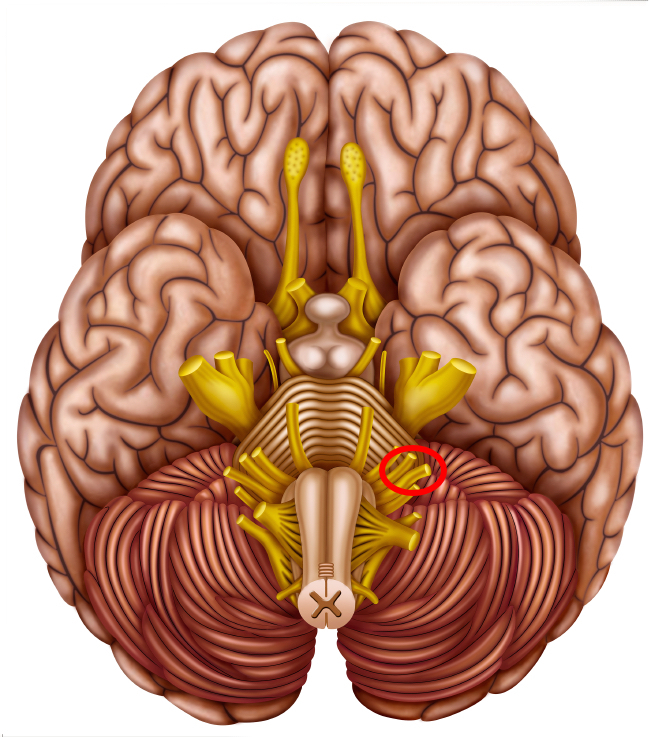

This picture shows the base of the brain with the cranial nerves emerging from it. The hearing and balance nerve is circled.